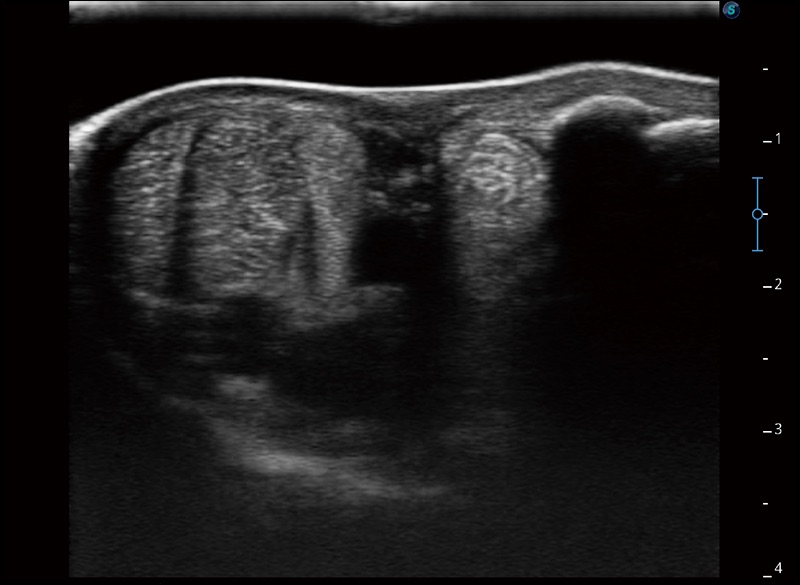

α1卓越的图像质量和便捷的工作流程,使每位宠物医生都能轻松扫查。其全面的兽用应用功能和紧凑型的结构设计,可以满足动物检查的多种需要。专业的预设检查模式和多领域测量软件包有助于为不同类型的动物提供检查, 让宠物医生能够出色的完成工作。

扩展成像

支持线阵和凸阵探头,一键操作即可获得更宽的图像视野

穿刺针增强

高清显示穿刺进针情况